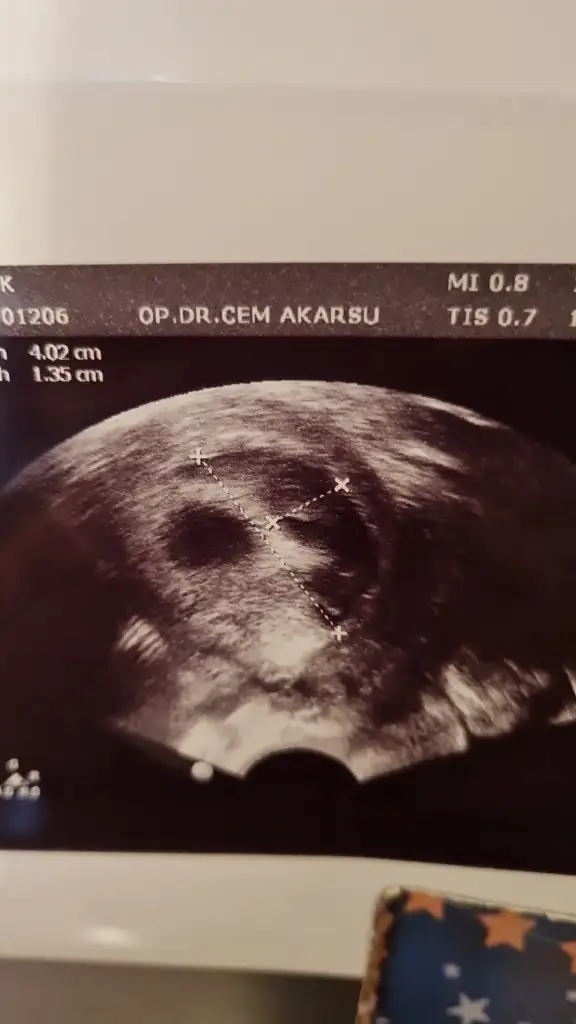

arkadaslar bebegimi ilk gormeye gittigimizde 5+4 tu yolk kesesini gorduk ve gayet iyiydi hersey smdi 7+2 de hem bebisimi hemde kalp atisini gormeye gitcektik 7+1 birgun once gece ani bi kanamayla acile gittik kanamam adet gibi yogundu ve asiri buyuk ciger gibi kan pihtilari dustu ertesi gun doktorumla randovumuz vardi zaten gittik bebisin kalp atisini duyduk bebekte iyiydi kesede zarar gormemisti ama kanama alanima acildeki doktorda kendi doktorumda cok buyuk dedi 4.2 cmye 1.35 cm cikti benim bebegim tup bebek gunde 3 kere yumurta toplamadan beri fitil seklinde progestan 200 kullaniyodum smdi + olarak progestan dex igne verdi gunde 1 adet doktorumun dedigi dinlenmem agir is yapmamam bebek eger saglikliyla bisey olmicagini soyledi hatta kanin akmasi hastalari korkutsada onu memnun ediyomus basinc olusturmuyomus boylelikle icerde bebek buyudukce rahimde daha fazla yer kaplamaya basladikca kanama dururmus bu boyutlarda bi kanama yasayan var mi yada boyle bi kanama yasayip sonrasi ne oldu kanama alaninin gorselini ekliyorum tarali alan

benim dun kontrolum vardi kanama alanimiz daha cok buyumus alanimiz onceden 4 x 1.3 cm di simdi 5 x 4 kusur dedi ama bebis gayet iyi benim doktorum kanin akmasini istiyoki birikmesin iceride basinc yapmasin diye birde akarsa daha hizli bosalir vucudun emmesini beklersek daha gec biter diyo o yuzden bence sizde korkmayin sizin cmleriniz nasil ben eski ve gunceli koyuyim tekrar ama bu kontrolde karindan baktigi icin sol saga dondu aynalama oldu yani siz tukenmezle cizili olan resmi kan alani sagda dusunun lutfen